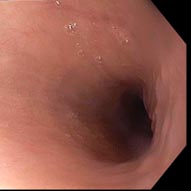

Снимок №1

Описание снимка №1